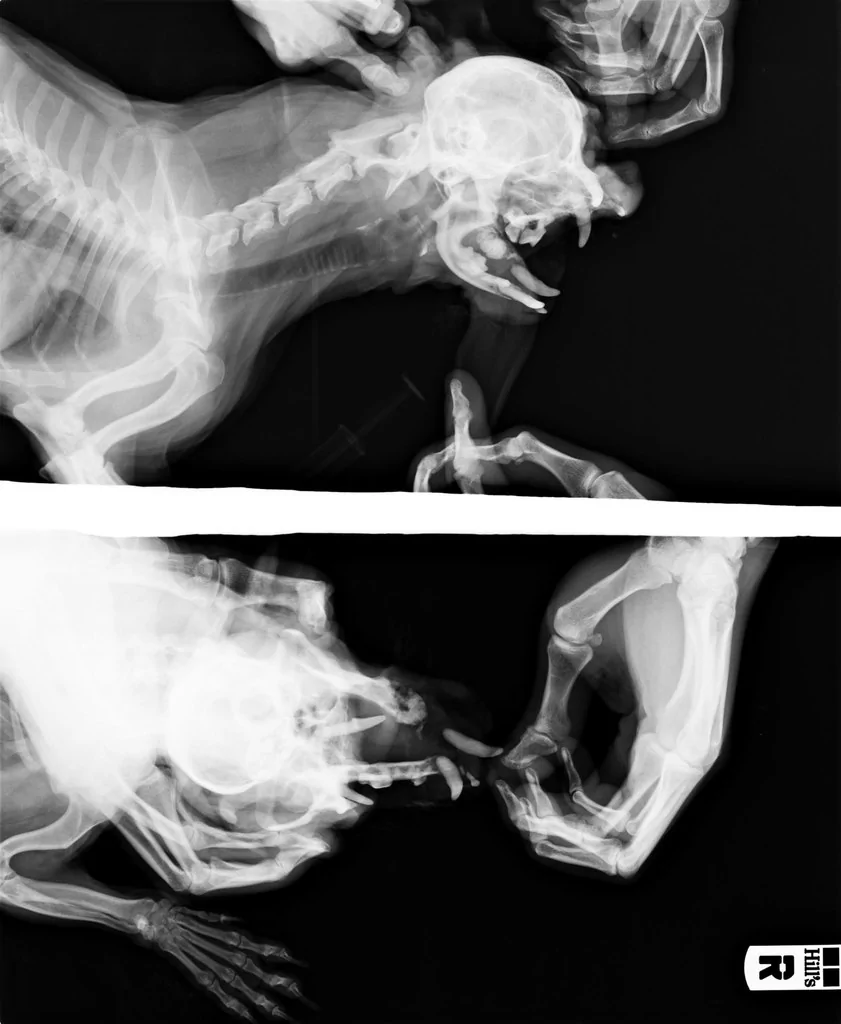

Рентгеновские снимки головы кошки в боковой проекции